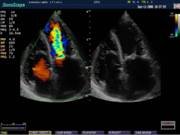

В Центре современных медицинских технологий «АКВА МЕД МАРИН» прием ведет врач УЗД высшей категории со стажем более 20лет - Пахалюк Александр Александрович. УЗИ-диагностика проводится на новейшем ультразвуковом диагностическом сканере Экспертного класса SonoScape S40Exp, в том числе и УЗИ детям с применением специальных детских датчиков. Цветной допплер помогает точной диагностике патологии сосудов и сердца у взрослых и детей.

Компания SonoScape уделила особое внимание допплеровским режимам и является экспертом в своем классе, что позволяет с легкостью, но в то же время с уникальной точностью проводить исследования с постановкой наиболее точного диагноза.

Ультразвуковые исследования, доплеровское сканирование сосудов в Центре современных медицинских технологий «АКВА МЕД МАРИН» выполняется при помощи первого и единственного аппарата в Керчи SonoScape S40Exp (экспертного класса, который оснащен множеством новейших функций, многократно улучшающих качество и информативность УЗИ-исследования).